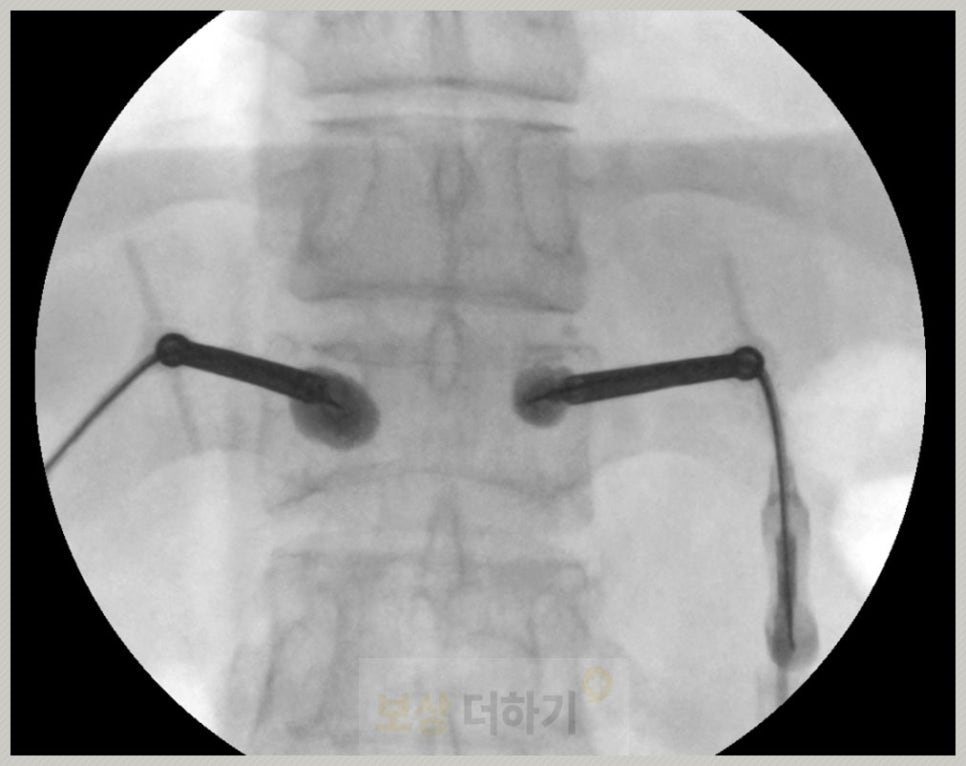

경피적 척추체 성형술 (풍선)

이분은 골다공증이 있었기 때문에 심한 통증 조절과 빠른 일상으로의 복귀를 위해 척추체 성형술을 시행하였습니다. [경피적 풍선 척추체 성형술]이란 무너진 척추체 안에 풍선을 넣어 공간을 만든 후에 그 자리에 골시멘트를 주입하여 척추를 단단하게 고정하는 시술입니다.

📝 골다공증 환자, 척추체 성형술 이유 ✔ 보존 치료만으로는 회복이 더딤 침상 안정, 보조기, 약물로도 통증 조절이 잘 안되거나 장기간 누워 있어 근육 위축, 폐렴 등 합병증 위험 있음 ✔ 척추 안정화 및 빠른 통증 감소 골시멘트를 주입, 뼈를 단단히 고정하면 골절 부위가 안정화되며 통증이 즉각적으로 완화됨 ✔ 척추 변형 (후만증) 진행을 예방 무너진 척추체 높이를 일부 회복시킴, 척추가 점점 주저앉아 등이 굽는 후만 변형 악화를 줄임